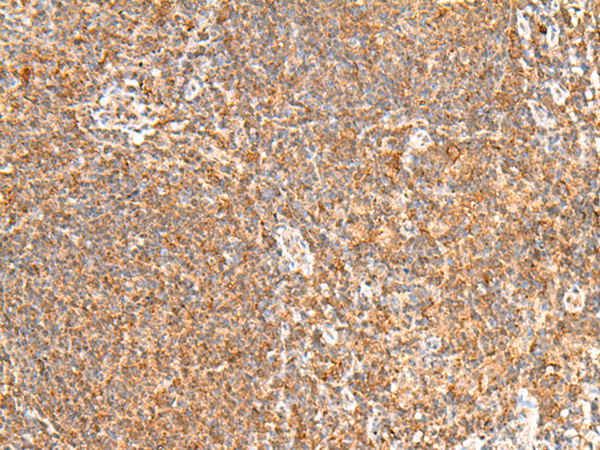

分类: 科研抗体货号: P43576别名: EIF3EIP; EIF3S11; HSPC021; HSPC025; MSTP005; EIF3S6IP应用: IHC反应种属: Human, Mouse